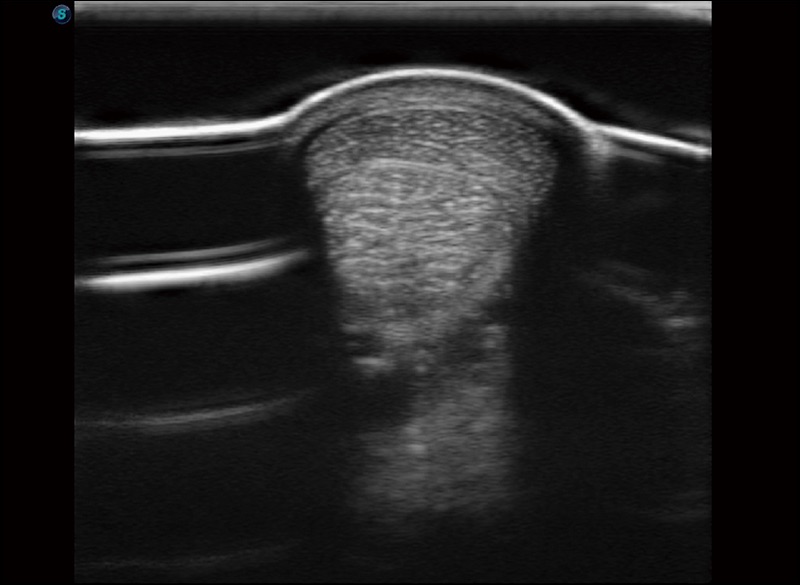

α1卓越的图像质量和便捷的工作流程,使每位宠物医生都能轻松扫查。其全面的兽用应用功能和紧凑型的结构设计,可以满足动物检查的多种需要。专业的预设检查模式和多领域测量软件包有助于为不同类型的动物提供检查, 让宠物医生能够出色的完成工作。

空间复合成像

优化不同角度的图像